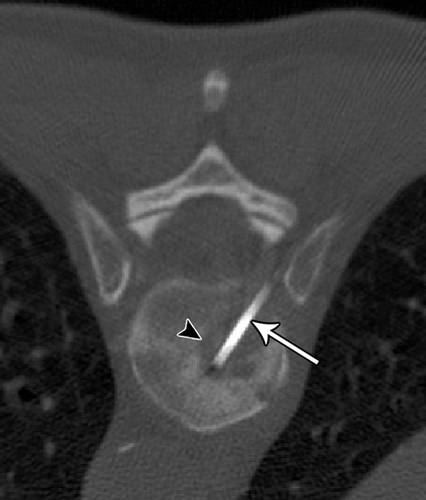

7 - 74岁男性成骨细胞性骨肉瘤穿刺。

![]()